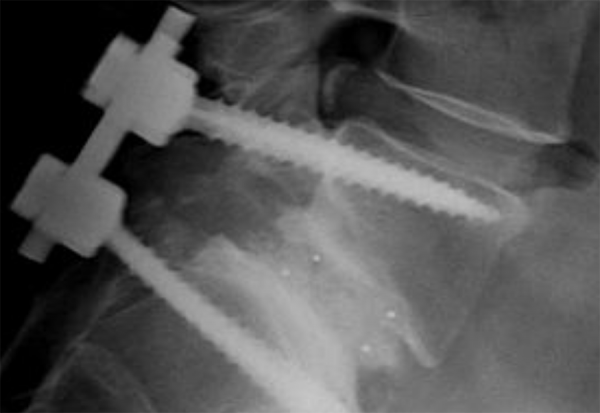

Η κυφοπλαστική είναι μια εξειδικευμένη ελάχιστα επεμβατική χειρουργική επέμβαση που εφαρμόζεται για τη θεραπεία καταγμάτων στη σπονδυλική στήλη, τα οποία προκαλούνται συνήθως από τραυματισμό, κακοήθειες κά